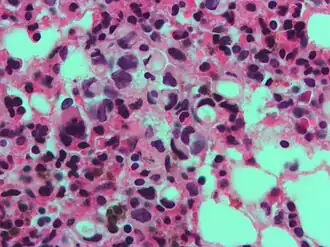

The name of the cell comes from its appearance; signet ring cells resemble signet rings. They contain a large amount of mucin, which pushes the nucleus to the cell periphery. The pool of mucin in a signet ring cell mimics the appearance of a finger hole and the nucleus mimics the appearance of the face of the ring in profile.

.jpg) Gastric signet ring cell carcinoma. H&E stain. Gastric signet ring cell carcinoma. H&E stain.

A signet ring-like foamy macrophage, which may mimic a cancer cell, but the texture of the nucleus is similar to that of a normal macrophage. A signet ring-like foamy macrophage, which may mimic a cancer cell, but the texture of the nucleus is similar to that of a normal macrophage.

High magnification micrograph showing signet ring cells, with clear cytoplasm, in metastatic breast carcinoma. H&E stain. High magnification micrograph showing signet ring cells, with clear cytoplasm, in metastatic breast carcinoma. H&E stain.